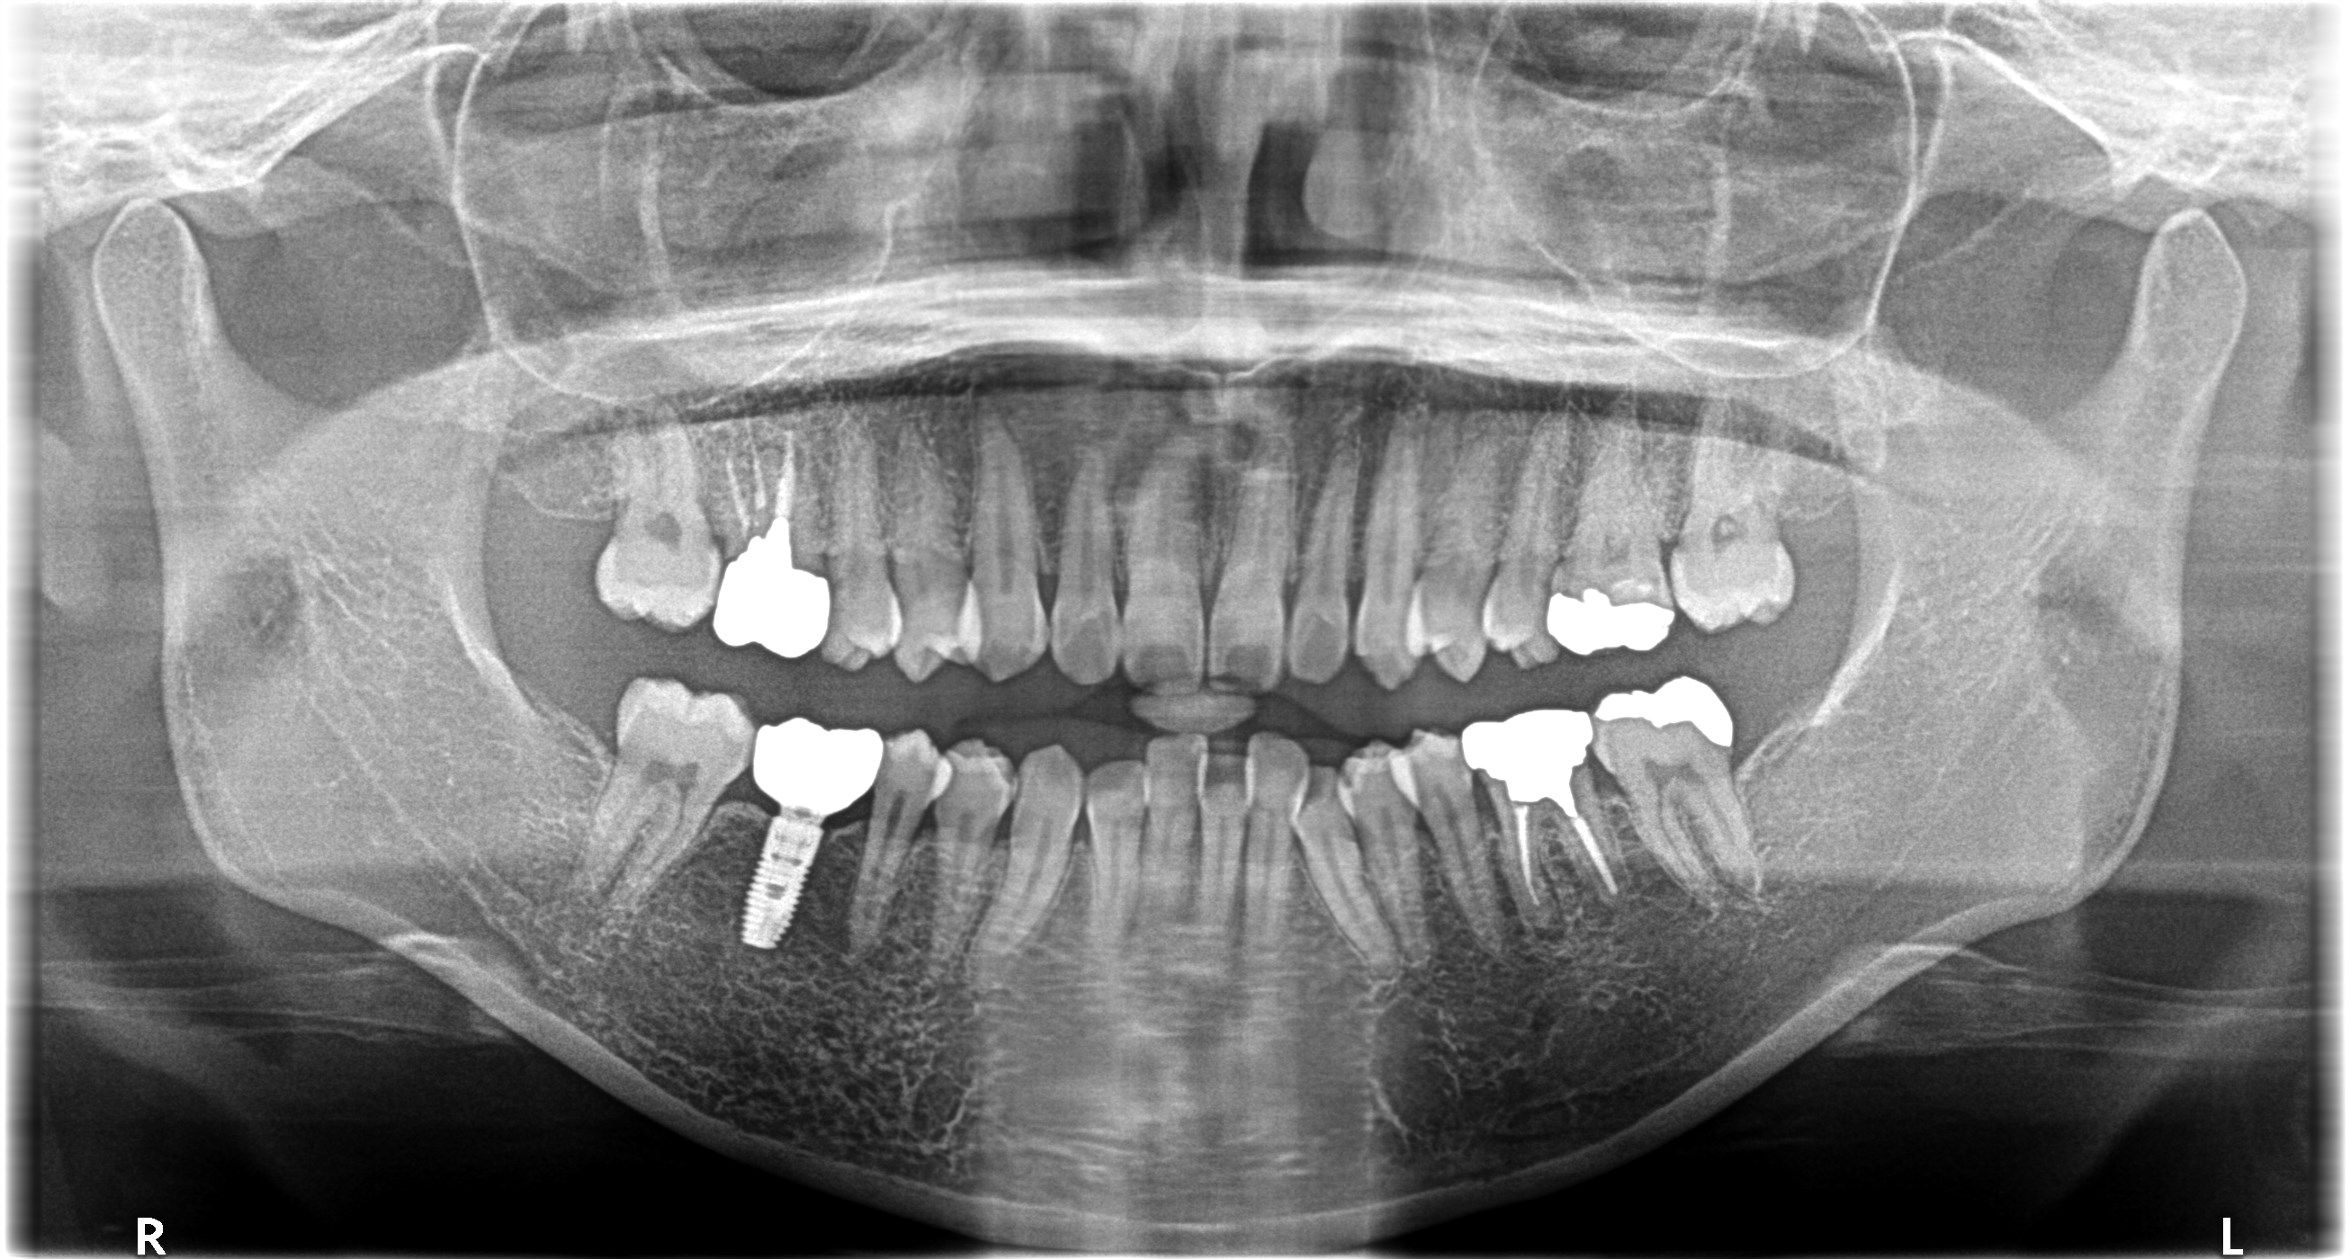

根管治療とインプラント、どちらを選ぶべき?

今回は 根管治療とインプラント、それぞれの特徴・メリット・デメリット を比較し、どのように選択すればよいのかをわかりやすく解説します。

① 根管治療とは?

根管治療は、歯の神経や血管が細菌に感染した場合に行う治療です。感染した神経を取り除き、歯の根の中を清掃・消毒して薬を詰めることで、歯を抜かずに残すことを目的としています。

② インプラントとは?

インプラントは、歯を失った部分の顎の骨に人工のチタン製のネジ(フィクスチャー)を埋め込み、その上に人工の歯を装着する治療です。自分の歯のように噛めるのが特徴です。

③ 年齢や口腔内の状態による選択の違い

どちらの治療が向いているかは、年齢やお口の状態によって変わります。

④ 当院での治療方針

名駅サランおとなこども歯科では、「残せる歯はできるだけ残す」 ことを基本方針としています。

これにより、根管治療の成功率を高め、歯を残す可能性を最大限に引き出します。

こうしたケースでは、無理に歯を残すことよりも 抜歯+インプラント の方が将来的に有利になると判断し、ご提案します。

つまり、当院では「根管治療かインプラントか」の二択ではなく、お口全体の健康と将来の予測をふまえて最適な選択 を一緒に考えていきます。